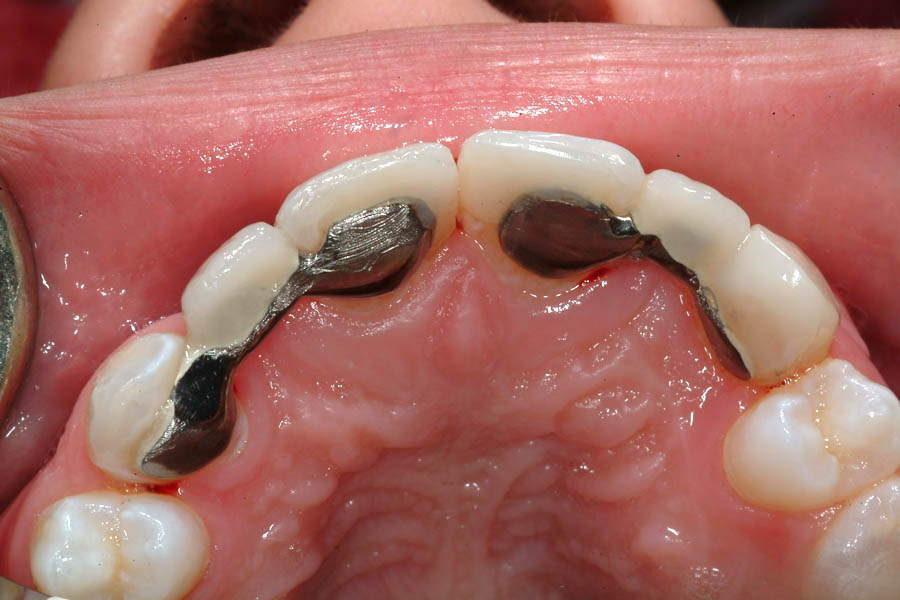

La momentul prezentării în clinică, în decembrie 2002, pacienta avea 8 ani şi o lună şi suferea de fibroză chistică şi de o deficienţă de dezvoltare a etajului mijlociu al feţei. Aceasta prezenta o anomalie de clasa I care mima o anomalie de clasa a III-a. Incisivii centrali, laterali şi caninii temporari maxilari, precum şi molarii prim şi secund de pe partea stângă erau în ocluzie inversă. În plus, pacienta prezenta coloraţii ale dinţilor de etiologie idiopatică (fig. 1). Autorii au considerat coloraţiile ca fiind de suprafaţă, extrinsece şi nu determinate de fibroza chistică, dovadă îndepărtarea acestora prin periaj profesional. Radiografia panoramică efectuată cu 6 luni înainte de prezentarea în clinica stomatologică relevă anodonţia incisivilor laterali superiori şi a premolarului secund drept inferior, ca şi posibila incluzie a caninilor maxilari, în special a celui stâng (fig. 2).